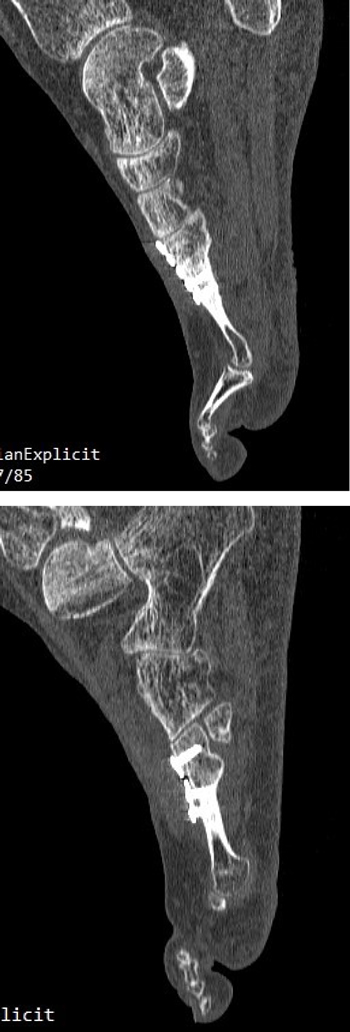

Con fecha 16 de junio de 2015 se realizó la intervención quirúrgica bajo sedación consciente y con anestesia raquídea. Se usaron 2 g de cefazolina intravenosa como profilaxis antibiótica previamente al inflado del torniquete colocado en el tobillo a una presión de 230 mm Hg. Se realizaron cuatro incisiones: una incisión medial para la corrección del hallux abductus valgus, una incisión dorsal sobre segundo metatarsiano, otra incisión dorsal sobre cuarto metatarsiano, y una cuarta incisión en la zona posterior lateral del calcáneo derecho para la obtención del autoinjerto. A través de la primera incisión, se realizó la corrección del hallux valgus con liberación de la contractura lateral vía intrarticular, liberando el ligamento suspensorio y con tenotomías de la cabeza lateral del flexor corto del hallux y del abductor del hallux, junto con osteotomía de Scarf en el primer metatarsiano fijado con un tornillo tipo Herbert (3.0 mm META SCREW® con rosca larga de 20 mm) (Debramedix; Almoradi, Alicante, España) y osteotomía de Akin en la falange proximal (fijado con grapa medial). A través de la segunda incisión en el segundo metatarsiano, se realizó desbridamiento y limpieza de la zona de la pseudoartrosis (Figura 3A). Se midió la longitud del defecto óseo, que era 7 mm, y se obtuvo el autoinjerto de calcáneo del pie derecho (Figuras 4A y 4B) para luego implantarlo en el metatarsiano (Figura 3B). El defecto de calcáneo fue rellenado con sustituto óseo sintético, una cerámica sintética de hidroxiapatita 65 % y fosfato tricálcico 35 % (CERAFORM®, Tecknimed; L’union, France). El autoinjerto de calcáneo utilizado es principalmente de hueso esponjoso y presenta hueso cortical obtenido de las paredes dorsal y lateral del calcáneo, de manera que se situó la porción del injerto con cortical en posición dorsal para resistir mejor las fuerzas de compresión a la carga. Se estabilizó con placa de bloqueo en “T” (miniplaca en T 2/4 orificios 30 x 5 mm con tornillo bloqueado de 2.0 mm) (Debramedix; Almoradi, Alicante, España)(Imagen 8). A través de la tercera incisión se realizó una estabilización del cuarto metatarsiano con placa recta dorsal (miniplaca recta 5 orificios 29 x 5 mm con tornillos bloqueados de 2.0 (Debramedix; Almoradi, Alicante, España). Se realizó finalmente un bloqueo postoperatorio local con 8 ml de bupivacaína 0.5 % junto con 2 cc de betametasona (Celestone®Cronodose®, Schering-Plough; New Jersey, USA). La Figura 5 muestra la radiografía postoperatoria.

El postoperatorio transcurrió sin incidencias y se realizaron curas postoperatorias con suero fisiológico y povidona yodada a los 7, 21 y 49 días postoperatorios. A las 6 semanas y 2 días (30 de julio de 2015) se realizó TAC de control que fue valorado el 7 de agosto de 2015 (7 semanas y 3 días tras la intervencion). Este TAC evidenciaba buena integración del injerto. Tras este hecho, junto con la favorable evolución clínica, se permitió a la paciente la carga parcial con bota tipo Walker durante 3 semanas para posteriormente comenzar a utilizar calzado convencional de forma progresiva.

A los 5 meses de la intervención se solicitó nuevamente un TAC comparativo que se realizó el 20 de noviembre de 2015 (Figura 6) que evidenció la integración completa del injerto y la consolidación del 4.º metatarsiano. La evolución clínica de la paciente fue muy positiva con ausencia completa de dolor realizando todas las actividades de la vida diaria con normalidad. Con fecha 25 de mayo de 2016 (11 meses postoperatorios) se realizó última visita de la paciente encontrándose esta en perfectas condiciones y dando el alta a la paciente. La paciente ha sido seguido posteriormente con revisiones anuales durante 4 años (hasta 2019) sin ninguna alteración.

Imagen 6. TAC postoperatorio a los 5 meses. 6A. Imagen del 2º metatarsiano que muestra integración del injerto con la placa dorsal. 6B. Imagen del 4º metatarsiano que muestra consolidación del 4º metatarsiano.